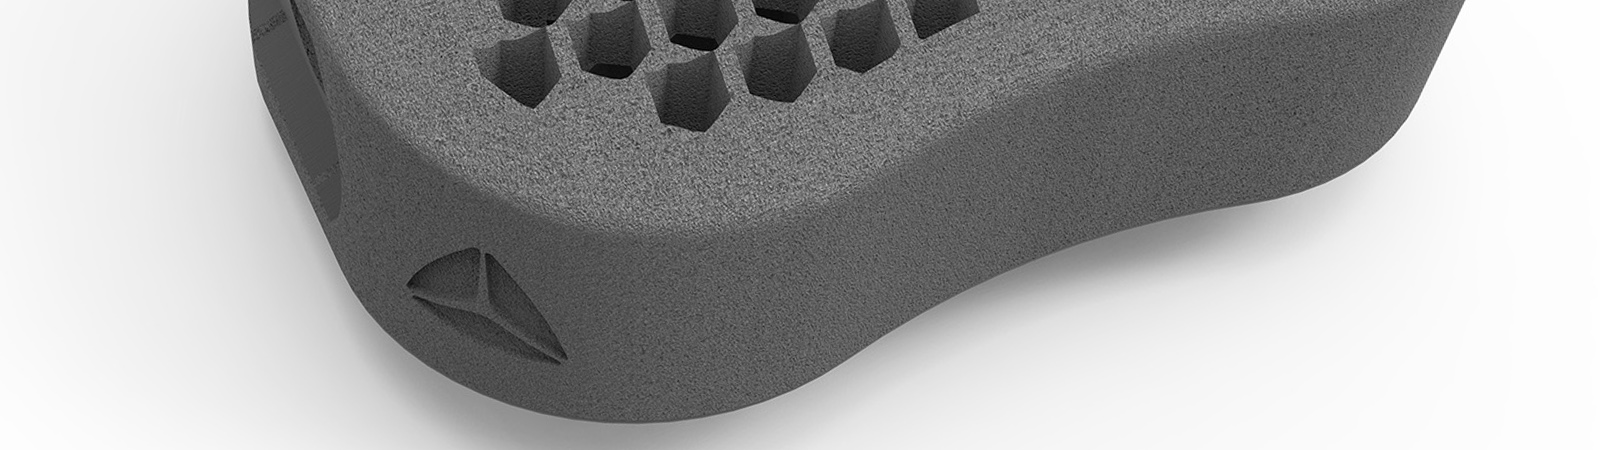

Alle Modelle nun mit der patentierten hygroskopischen Struktur. Diese Kapillarwirkung beeinflusst das Einwachsverhalten positiv ohne Verwendung von autologem Knochen.

HYGROCervicaler Cage aus Titan

Hygro ist ein Unikat auf dem Markt. Wie der Name schon sagt werden durch eine spezielle Anordnung der Lamellen im Inneren des Cages optimale hygroskopische Eigenschaften erziehlt. Eine Fusion wird hierbei erzielt ohne den Cage mit autologem Knochen oder Knochenersatzmaterial zu befüllen.